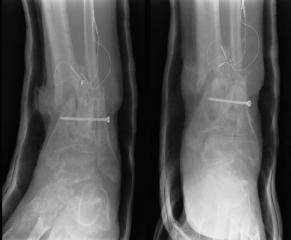

Pre-corrective surgery X-Rays of the damaged right & left legs / ankles

These x-rays were taken at Dr Armendariz’s office, just prior to performing any corrective surgery. As can be seen in these images,

there was no tibia bracing provided by Dr. Keller. Liam was released from Dr Keller’s care with instructions that full weight bearing could

be accomplished within 2 months of Keller’s last surgical procedure. The best example to examine is the second image (from the left) of the

top how. Notice how the bones that should be aligned with the tibia are in fact on the other side of the leg. The third image shows how badly

Liam’s left foot was twisted as a result of the pool placement of the external fixation. What is not obvious is that the screw at the bottom

of the plate on the right fibula missed being screwed into the plate.